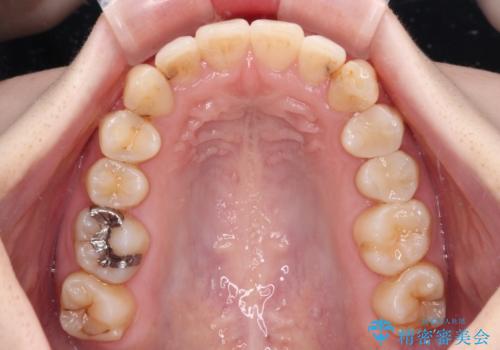

- 前歯のデコボコをクロスバイトを気にして来院された患者様です。

上顎骨の横幅が狭く、上下ともに内側に倒れ込んだ混み合った歯列となっていました。

矯正治療後には、目立つ銀歯と隣接するむし歯をセラミックインレーにて修復治療することとしました。